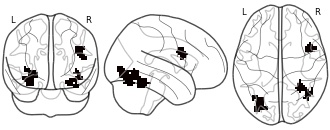

"name": "VBM_HeterogeneityMap",

"description": "Abnormal gray matter in BPD. Brain regions with significant heterogeneity (i.e. between-study variance) in the comparison of patients with BPD and healthy controls. Results are thresholded at at p<.005 & k>20. Note: Results are based on meta-analysis of group comparisons. Note2: Results were updated (see Erratum for this publication)",